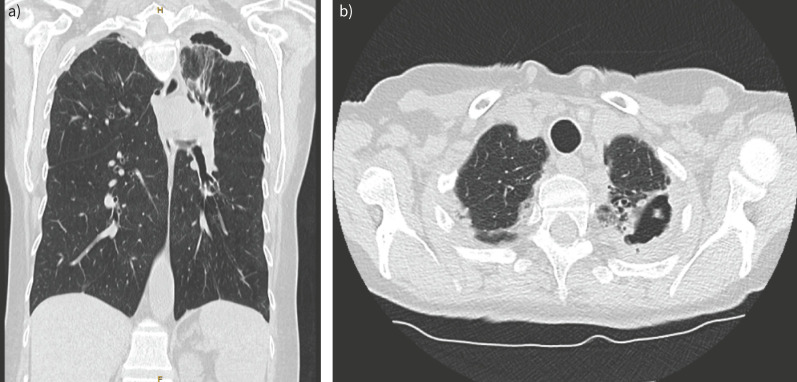

Chronic pulmonary aspergillosis has a range of manifestations from indolent nodules to semi-invasive infection. Patients may be asymptomatic or have chronic symptoms such as cough and weight loss or present with life-threatening haemoptysis. The physician can choose from a range of available therapies including medical therapy with antifungals, minimally invasive therapy with intracavitary antifungal therapy and surgery involving open thoracotomy or video-assisted thoracoscopic surgery. The patients with the most severe forms of pulmonary infection may not be surgical candidates due to their underlying pulmonary condition. The management of haemoptysis can include tranexamic acid, bronchial artery embolisation, antifungals or surgery. There are few controlled studies to inform clinicians managing complex cases, so a multidisciplinary approach may be helpful.